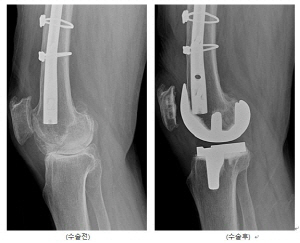

KakaoTalk_20220825_105904090

영상장비 및 로봇인공관절수술 술기의 발달로 외상성관절염 환자도 철심 제거 없이 인공관절수술을 받을 수 있다. /사진=서울부민병원 로봇수술센터

하지만 최근 영상장비 및 로봇인공관절수술의 발달로 외상성관절염 환자도 철심 제거 없이 인공관절 수술을 받을 수 있다는 것이 궁 센터장의 설명이다. 그는 "컴퓨터기술의 보조(로봇, 네비게이션, 3D맞춤형 수술기구)로 무릎주위에 금속고정물이 있는 환자도 안전하게 인공관절 치환술을 받을 수 있게 됐다"며 "CT기반의 사전정보 분석이 로봇인공관절수술의 적용범위와 수술성공에 큰 역할을 하고 있다"고 말했다.